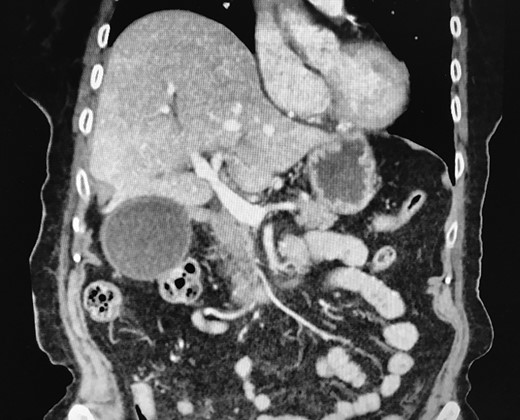

A Caucasian 92-year-old lady attended the emergency department with acute onset epigastric/right hypochondrial pain, waking the patient from sleep. The pain was described as being constant since onset and radiated through to her back. The pain was immediately followed by profuse and intractable vomiting. There had been no previous episodes of similar pain and she had been well in the preceding days. Her past medical history included an open appendicectomy, hypertension, GORD, previous TIA, left carotid endarterectomy, peripheral vascular disease and a L2 crush fracture. The patient denied fevers/rigors and had no recent history of lower urinary tract symptoms or altered bowel habit. The vital signs recorded for the patient were within normal limits and she was afebrile. On examination of the patient’s abdomen it was noted that the abdomen was soft and not distended, with diffuse tenderness down the right side. The gallbladder was also palpable to the right iliac fossa. The white cell count was mildly elevated at 13.2, while there were no electrolyte abnormalities and no renal or liver function derangement evident on blood tests. A CT scan of the abdomen and pelvis (Fig. 1) was arranged with contrast and was reported as showing a ‘distended gallbladder with prominent wall thickening and mild adjacent inflammatory change. The appearances are most consistent with cholecystitis’. An ultrasound was then performed that demonstrated a calculus together with minor gallbladder wall thickening but no evidence of biliary ductal dilatation. Thus, the patient was started on intravenous antibiotic therapy as per local guidelines for a presumed diagnosis of acute cholecystitis and admitted under the care of the general surgeons. The patient was reviewed on rounds the following morning and was noted to have increasing pain despite analgesia associated with tachycardia, tachypnoea and diaphoresis with a peritonitic abdomen. The white cell count was now elevated at 17.6 with a CRP of 198 and the liver function tests remained within normal limits. The patient was reimaged with a further CT abdomen/pelvis with contrast which was reported as showing ‘cholelithiasis and choledocholithiasis with intra and extra bile duct dilatation as well as marked gallbladder distension and pericholecystic fluid’. An emergency laparotomy was performed with findings on entry of a non-viable and gangrenous gallbladder secondary to gallbladder volvulus. The images below show the volvulus as well as the cystic duct and cystic artery after being detorted (Fig. 2). The patient was managed in ICU immediately postoperatively but medically fit for discharge after five nights in hospital.